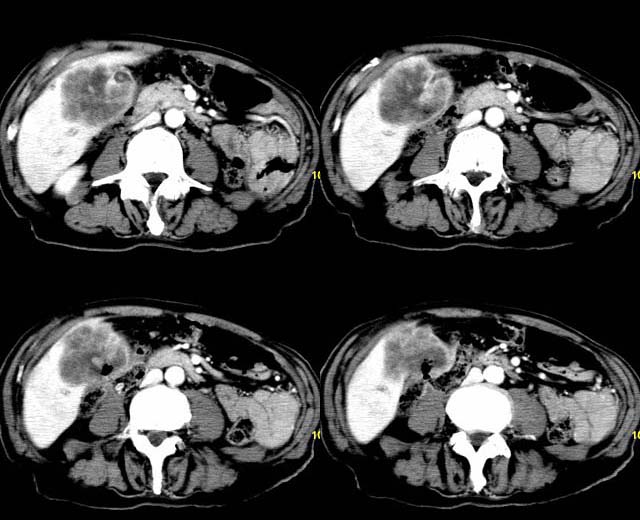

以下是引用余辉在2007-12-6 22:23:00的发言:[br]胆囊内多枚结石影,胆管全程扩张,右肝内病灶强化符合脓肿表现现(左肝病灶图像未传完),考虑急性梗阻性化脓性胆囊胆管炎合并肝多发脓肿(建议补传左肝病灶图像)